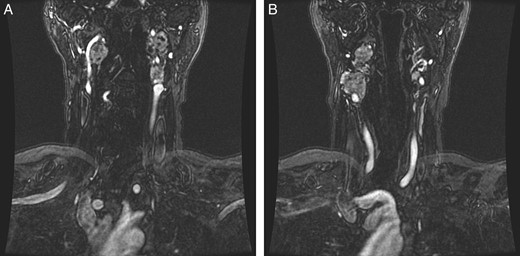

Repeat magnetic resonance imaging (Figs. 3 and 4) showed increased left-sided carotid PGL, significant extension into the jugular foramen and skull base, and associated high-grade tumor compromise of the left internal carotid artery; no radiologic evidence suggested intracranial ischemic sequelae. Computed tomographic (CT) imaging showed infiltration of the left petrous and clivus regions of the skull (Fig. 5). Findings were compatible with progression of the previously known tumor.

(A and B) Magnetic resonance images, sagittal and coronal planes, show increased left-sided carotid PGL, with significant extension into the jugular foramen and skull base.

Magnetic resonance angiogram, coronal plane, shows tumor compromise of the left internal carotid artery.